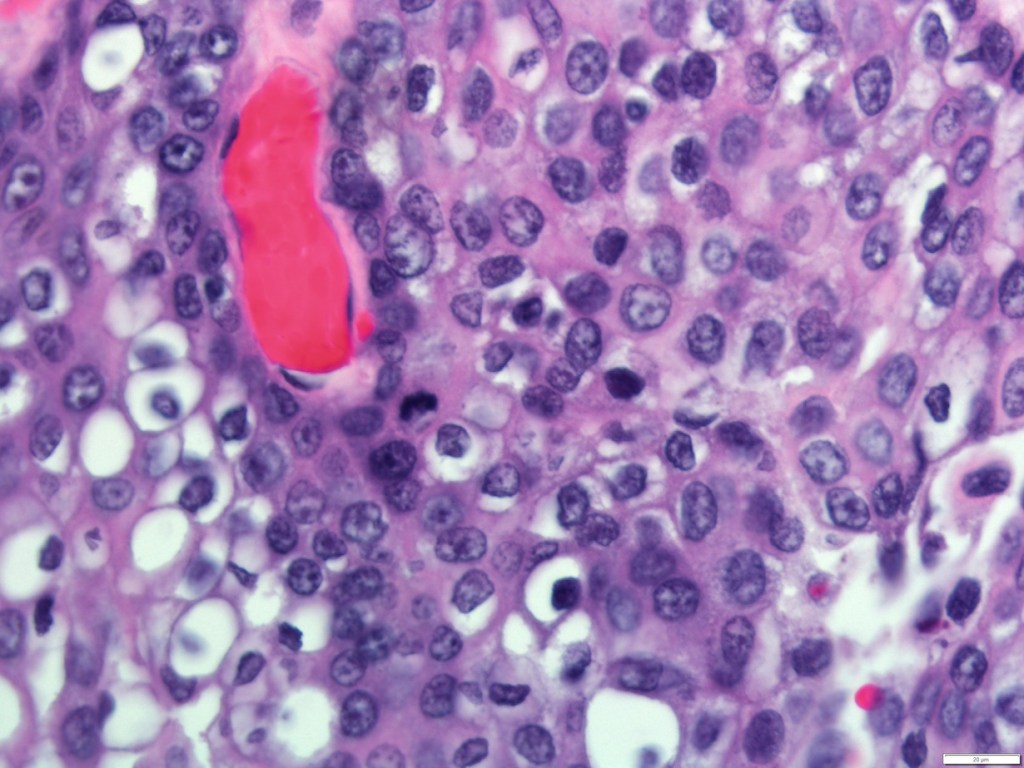

- Histologically:

- They are characterized by a mixed population of cells, including:

- Mucin-producing cells

- Epidermoid cells with squamoid differentiation

- Clear cells

- Intermediate cells:

- That may predominate in numbers

- Are believed to be the progenitor of the other types of cells

- No myoepithelial cells are present